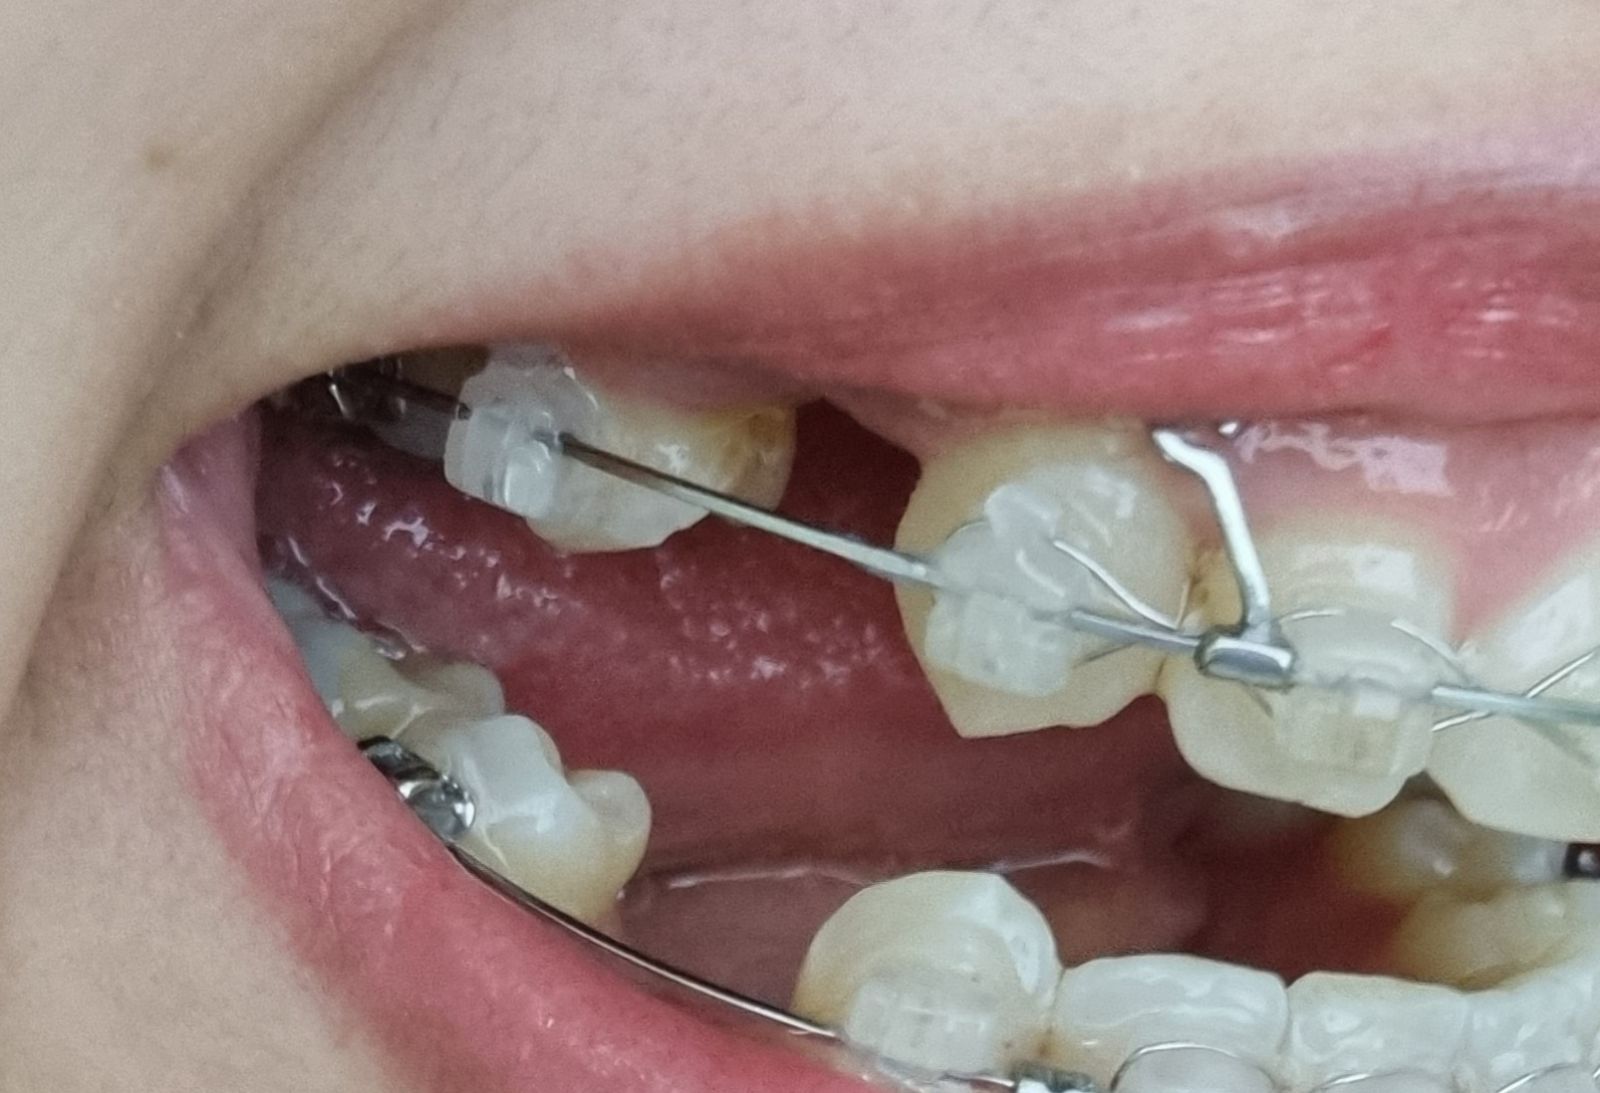

저는 지금 사진에서 보이는 것 처럼

잇몸에 미니스크류를 식립한 뒤에

가벼운 고무줄을 걸어서 위, 뒤쪽으로 텐션을 주고 있는 상태입니다.

2022/10/11

2022/11/07 같은 부분의 한달 사이 변화입니다.

각도에 따라 치아의 벌어진 정도가 달라 보여서

어느정도 변화가 있는지는 잘 모르겠어요.

제 눈에는 거의 그대로로 보이는데

원장님은 0.5cm 정도 줄어들었다고 합니다.

참고로 왼쪽에 잇몸 염증으로 인해서

스크류 뒤로 철사를 연결한 부분은

잘라내지 않고 그대로 철사 뒤에 고무줄을 하고 있습니다.